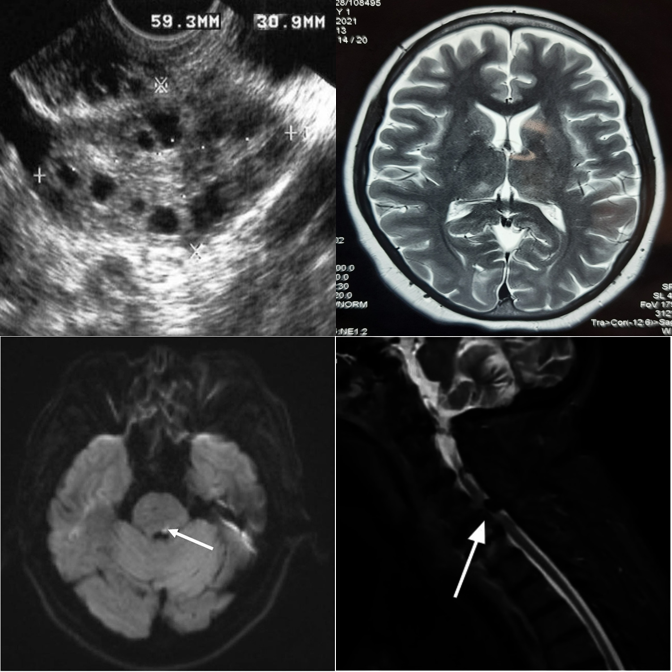

✓ Answer: bottom-left — an MRI scan among CT scans.

MedObvious abstracts multi-view clinical workflows into small grids where the model must identify an outlier — or correctly state that none exists.

Each tier introduces new complexity. Real examples from the benchmark are shown alongside each tier description.

Basic modality mismatches in 2×2 grids. E.g., one MRI scan among CT scans.

Broader modality pool with finer intra-class appearance variability in 2×2 grids.

Dense 3×3 grids with 8 distractors. Systematic comparison is essential.

Anatomy and viewpoint mismatches. E.g., one abdomen CT among chest X-rays.

High-saliency clinical failures: surgical hardware, fractures, gross pathology.